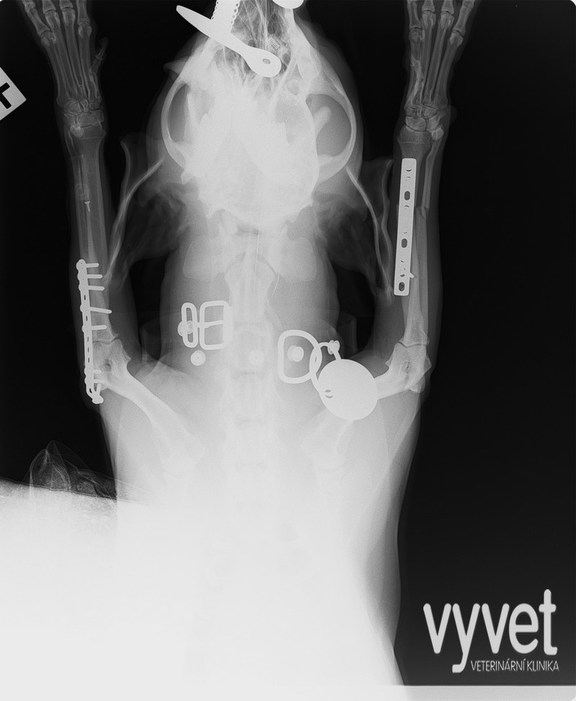

Nejčastějším problémem dlouhých kostí jsou zlomeniny (fraktury)

Rozdělujeme je do několika skupin podle charakteru, množství fragmentů, průběhu linie lomu, dislokace, stability atd.

Je mnoho popsaných metod fixací fraktur. Neinvazivní metodou je přikládání fixačních obvazů a kastů. Tento typ fixace však není ideální, protože nejsme schopni u zvířat zabezpečit dostatečně dlouhou dobu klidu pro srůst kosti. Ideální metodou je invazivnější přístup a to chirurgická repozice s následnou fixací osteosyntetickým materiálem.

Na našem pracovišti používáme zejména ploténky a hřeby.